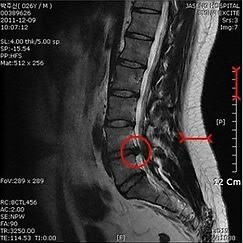

박 시장 측은 그동안 `무대응'으로 일관해왔으나 의료계에서까지 MRI(자가공명영상진단)의 진실 여부에 대해 의혹을 제기하자 변호사를 선임해 적극 대응하고 있다.

박 시장 아들의 변호를 맡은 엄상익 변호사는 "병무청 의료진을 만나 자료가 모두 진짜라는 것을 확인했다. 박 시장 아들이 검사받은 장면이 찍힌 폐쇄회로TV도 있으니 (의혹 해소에) 자신 있다"고 말했다.